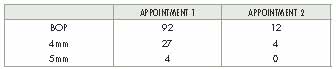

The success of a delicate periodontal procedure is dependent on both the skill of the clinician as well as several patient-associated factors. These include the past and present smoking status, systemic health conditions and compliance to post-operative protocols. Any one of the factors or in combination can delay or impair the healing process. However, common … Read more